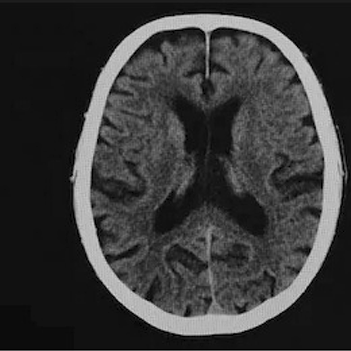

Table 6 Fused image output.

From: Multimodal medical image fusion combining saliency perception and generative adversarial network